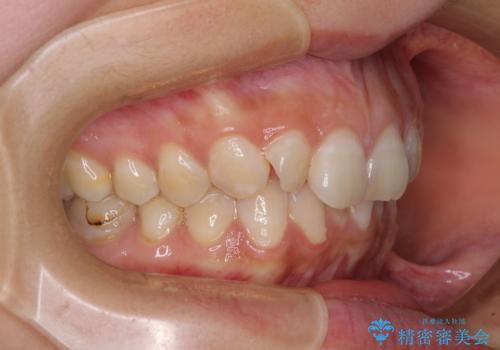

【モニター】隠れている下顎の前歯をインビザラインで改善

- 下顎の前歯が隠れていることと、デコボコを気にして来院された患者様です。

銀歯やムシ歯処置の必要な歯が奥歯にあり気になっていたので、矯正治療の途中でセラミッククラウンへ変更し、その後歯列を仕上げていくこととしました。

咬み合わせと目立っていた銀歯が改善され、患者様には大変満足していただきました。